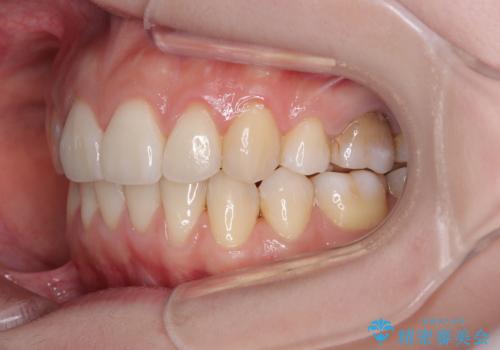

後戻りをインビザラインでスッキリした口元に

- 高校生の時に矯正治療を行ったものの、後取りをしてしまったとのことで来院された患者様です。

マウスピースでもワイヤー矯正でも対応可能でしたが、再度ワイヤーは装着したくないとのことでインビザラインにて矯正治療を行うこととしました。

舌の突出癖が原因で後戻りをしたため、舌のトレーニングをしっかりと行っていただき、口元の突出感を改善することができました。

インビザラインの装着時間が守れず、1年強で終わる予定でしたが、4年間を要することとなりました。